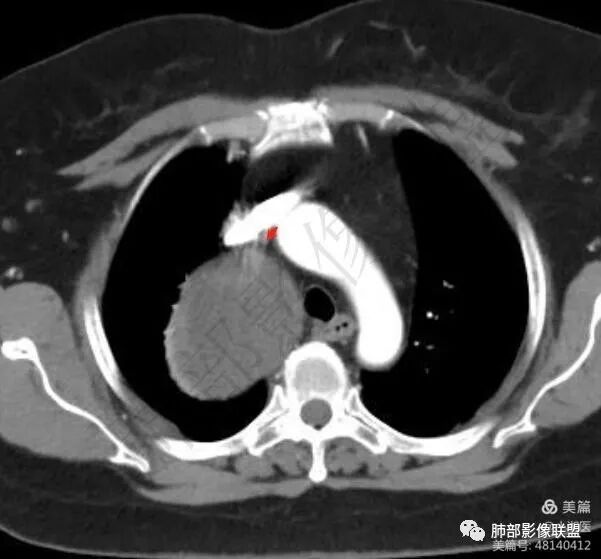

1. 右上胸廓入口区类椭圆形块影,边界清楚光整,纵向“嵌顿”于颈根部及上纵隔,向上推移右锁骨下动静脉,向外下方推移上肺胸膜及肺组织(肺血管、支气管),向前推移上腔静脉,界限清楚。

2. 块影不均匀轻度强化,可见较均匀实性区及液性密度区,未见积气、囊壁样结构、钙化或脂肪密度。可疑部分肋间动脉分支进入。

1.块影定位肺外-上纵隔。块影密度以及强化方式不支持胸腔内甲状腺肿、副节瘤、巨淋巴结增生、支气管囊肿以及畸胎瘤等。

肿块部位、密度以及强化特点聚焦于良性神经鞘瘤及孤立性纤维瘤。